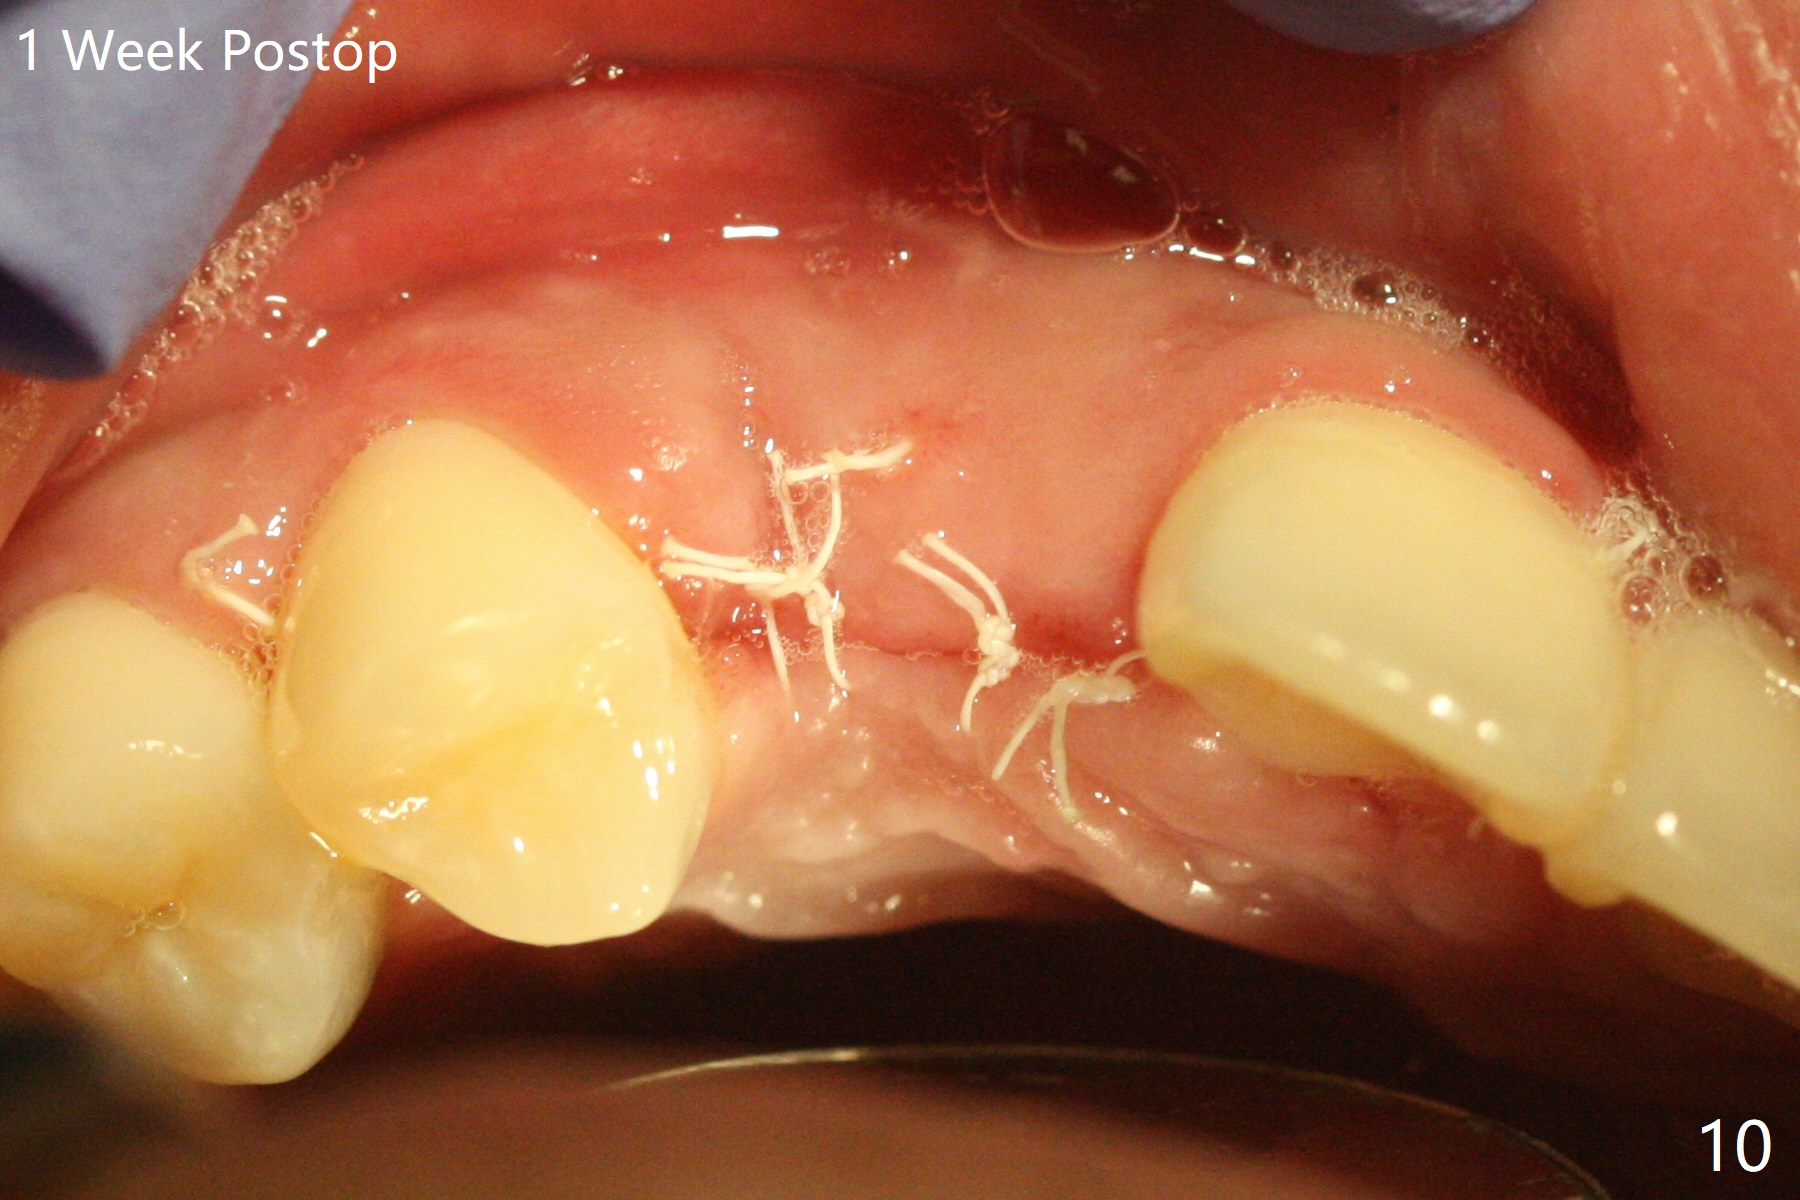

18岁男从外州大学回来,无症状,但是6号牙(右上尖牙)颊侧瘘道(图一,二(角化龈充分(箭头))),根尖片显示植体近中骨吸收(图三:*),而对侧植体仿佛骨整合(图四)。患侧切开后发现植体颊侧暴露,松动。拔除后骨缺损由粘性骨粉修复(图七,九:*),覆盖PRF膜(图七:P)和带钛网(图九:^)不可吸收膜(图五-七),后者用两个小钉子固定(图六(腭侧),七(颊侧),九),使用新的刀片和一个特殊尖头剥离器在颊侧骨膜下相当广泛分离,使用PTFE缝线,粘膜下水平褥式缝合之后(图八:箭头),多个垂直间断缝合,两个乳头垂直褥式缝合。术后一周伤口没有裂开,术后疼痛肿胀已经消退(图十)。术后十八天牙槽嵴仿佛比对侧还要宽(图十一,三与图十二,四(取模)对比)。术后5.5个月伤口没有裂开,牙槽骨,角化龈宽(图十六),与钛网和两个小钉子固定有关(图十五,十七)。CT显示牙槽骨只能容纳2.5或者3.0毫米植体(图十八)。11号牙植体牙冠粘固后没有骨质吸收(图十九),其实10,11号牙颊侧骨板隆起(图二十至二十二),而6植体失败,颊侧骨板吸收,甚至累及5号牙(图十七)。